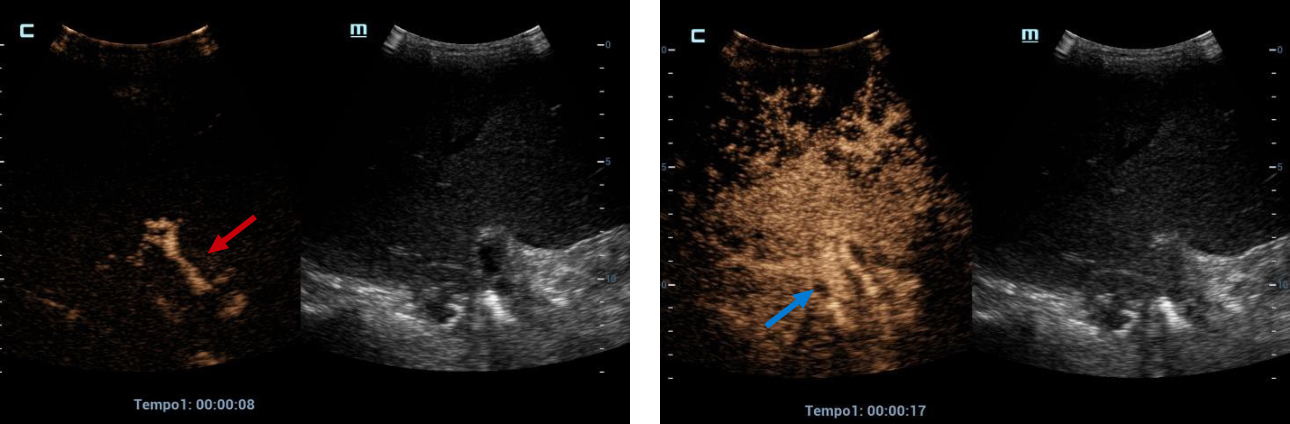

Therefore, it was decided to continue the assessment with contrasted ultrasound, an enhancement of vascular structures (Figures 2 and 3) can be observed about 8 seconds from the hepatic artery and 17 seconds from the portal vein without finding filling defects or areas of stenosis, however, in the portal phase of hepatic enhancement an area of hypoperfusion in segments 7/8, evidenced both by the live image and in the post-process of the perfusion curves and maps, this area was triangular morphology and subcapsular location (Figure 4), as well as the right hepatic artery is not visualized by this method, and the left was located at the level of the portal "H"(Figure 5).

CEUS, an earlier than expected enhancement of vascular structures is observed, the artery phase begins at 8 seconds (red arrow) and the portal/venous phase at 17 seconds (blue arrow).

Figures 2 and 3. CEUS, an earlier than expected enhancement of vascular structures is observed, the artery phase begins at 8 seconds (red arrow) and the portal/venous phase at 17 seconds (blue arrow).